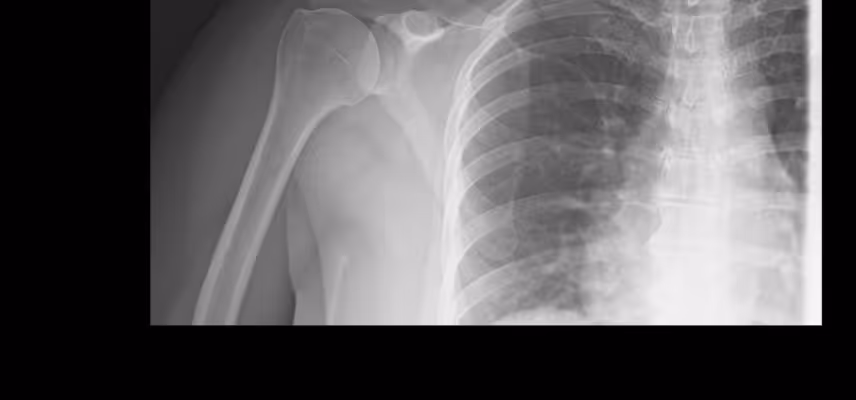

Nie, do fizjoterapeuty można umówić się bez skierowania. Jeśli posiadasz wyniki badań (np. USG, RTG, rezonans magnetyczny), koniecznie zabierz je ze sobą na pierwszą wizytę.